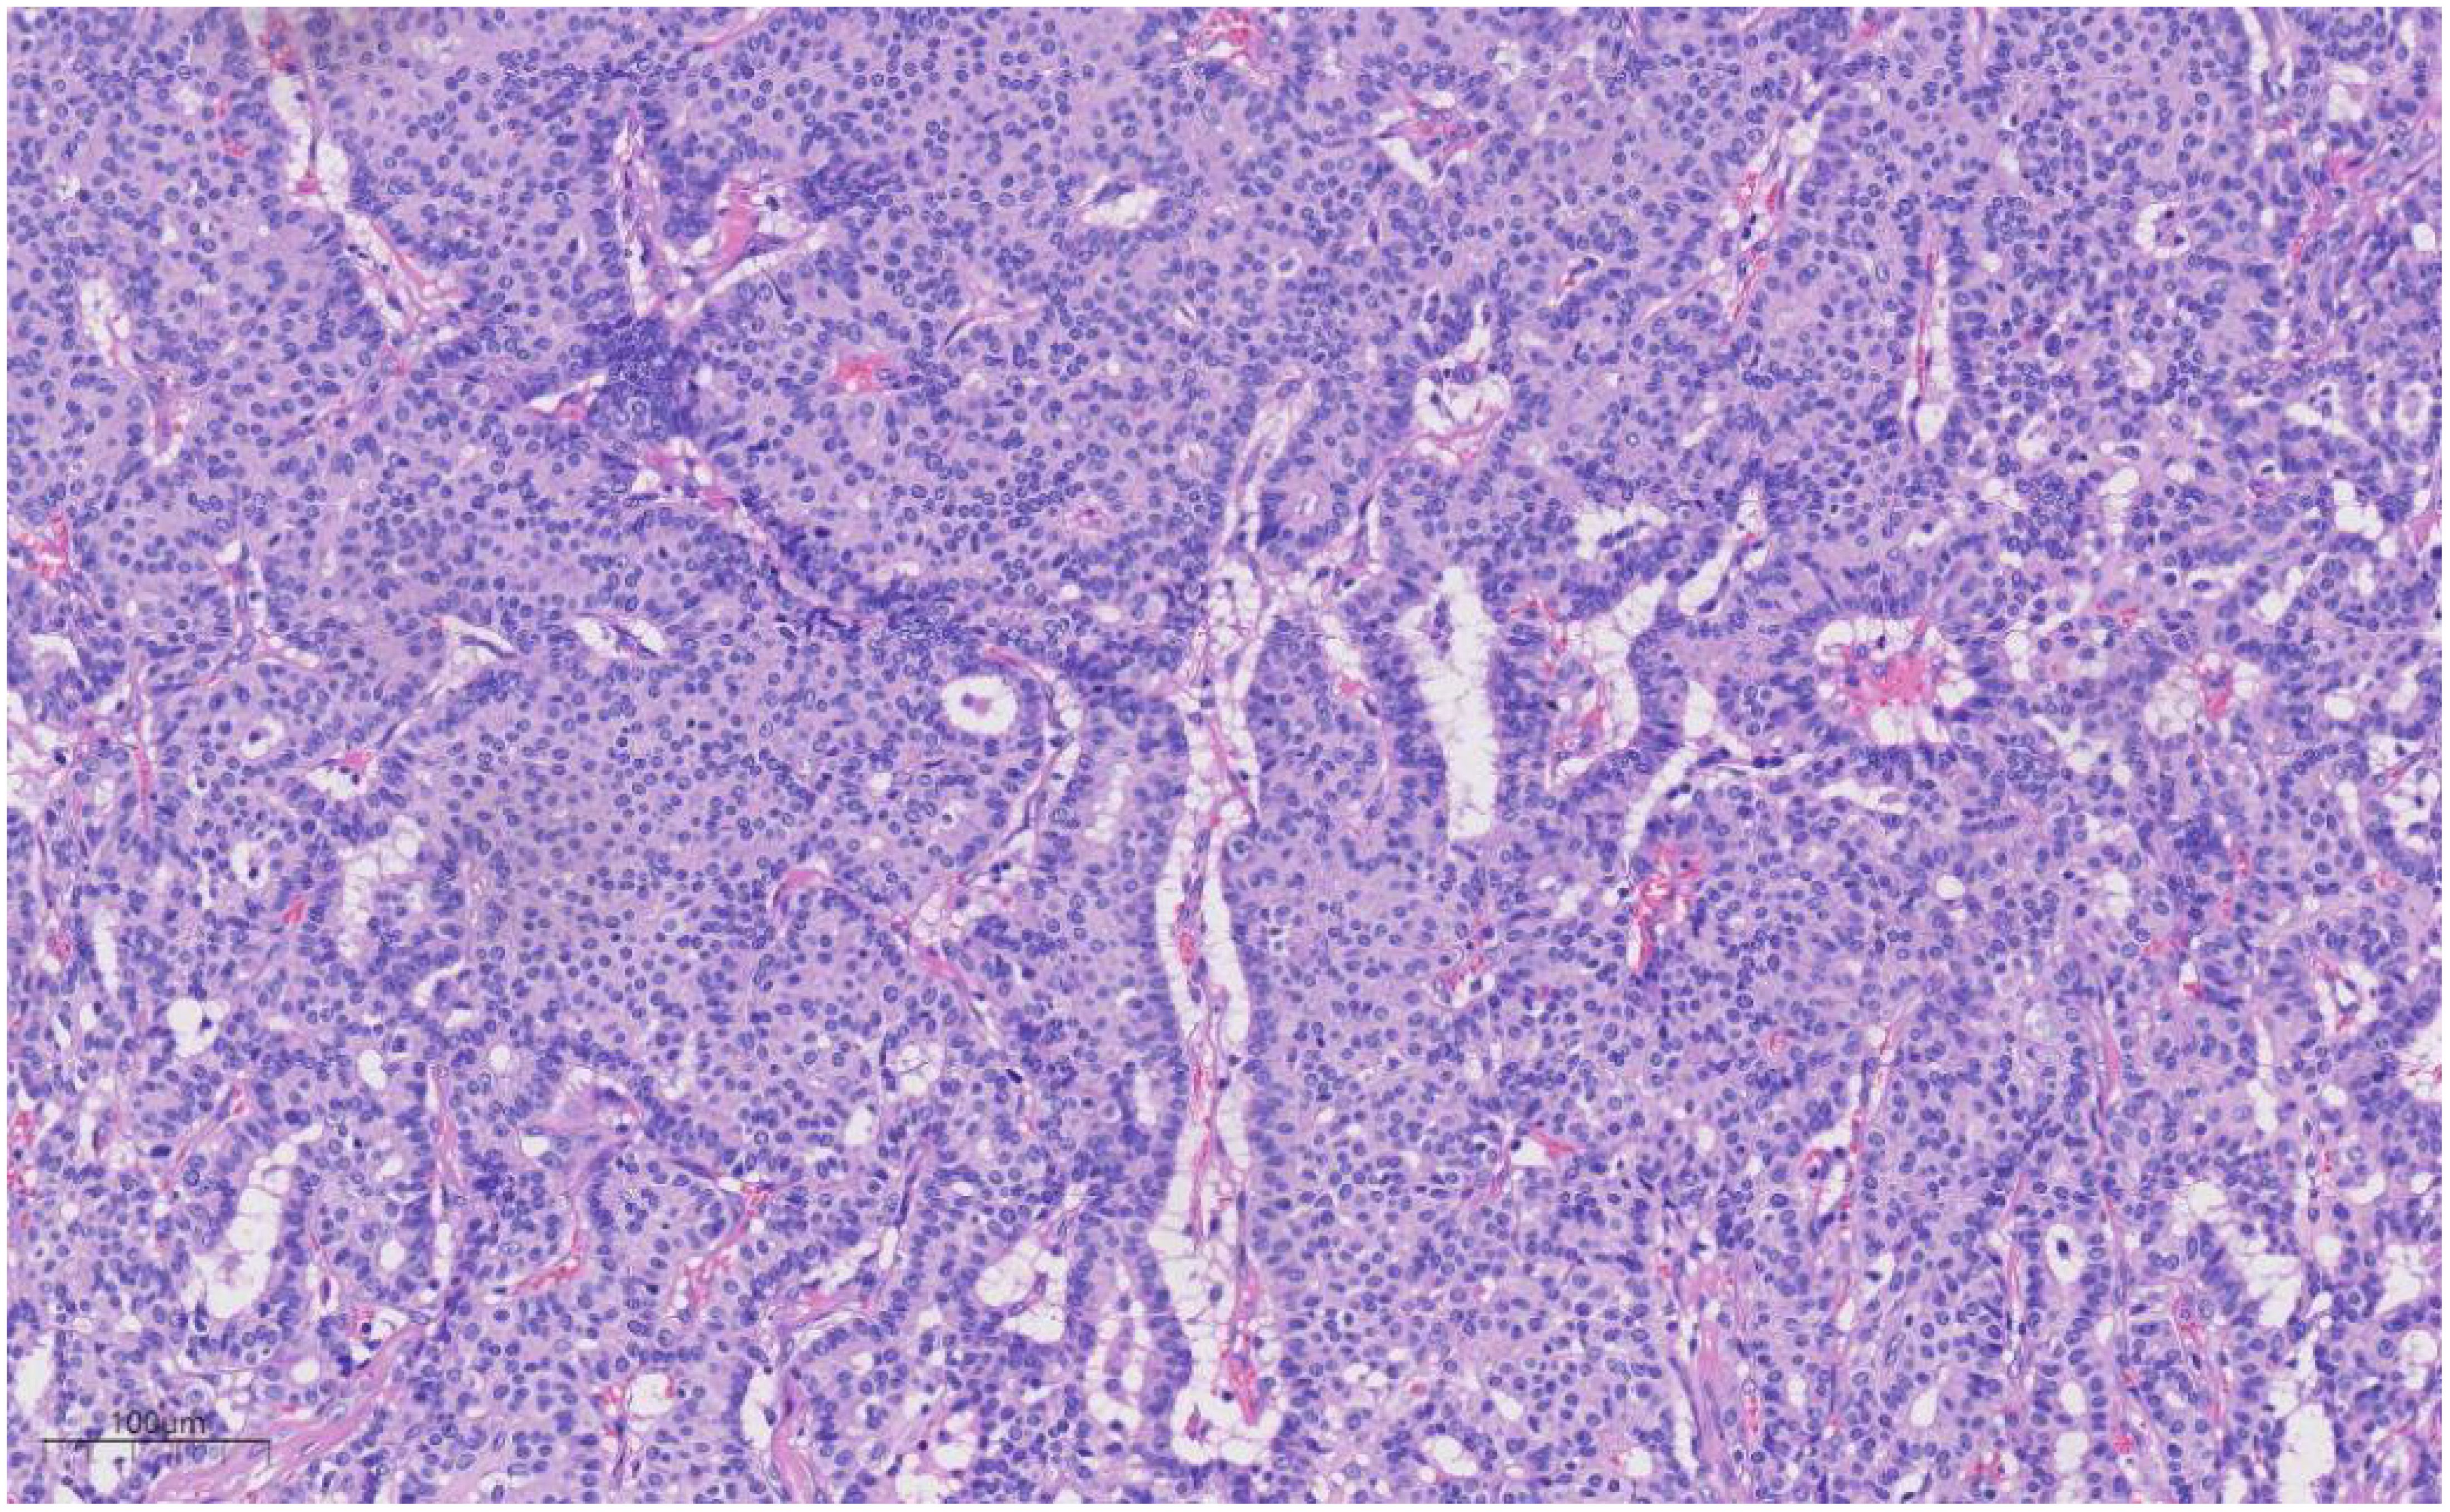

Histologically (Figures 24), the benign intraductal papilloma exhibited a papillary structure comprising two cellular layers: an inner epithelial layer and an outer basal myoepithelial layer, the latter extending continuously along the papillary axis and duct wall (Figures 2-4). The lesion contained low-grade DCIS, which demonstrated a papillary structure with solid or window-like formations. Nuclei were predominantly arranged in a polar orientation, slightly enlarged, oval to round in shape, uniform in size, and without overlap. Nuclear membranes were smooth, chromatin appeared uniform, varying from dusty to finely granular, and nucleoli were inconspicuous, with mitotic figures rarely seen. Notable areas of necrosis were observed in the axillary lymph nodes, surrounded by fibrous tissue or granulomas (Figure 5).

Figure 3

Microscopic view of liver tissue in hematoxylin and eosin staining, showing clusters of purple-stained nuclei and pink-stained cytoplasm. Blood vessels and liver cell structures are visible, with a scale bar indicating 100 micrometers.

Figure 3. Under medium magnification, low-grade DCIS was papillary and solidly arranged, with oval to round nuclei of uniform size and often arranged in a very high direction. H&E ×100.

Figure 4

Microscopic image of liver tissue showing clusters of cells with distinct nuclei. The stain highlights cellular structures in various shades of purple and pink, indicating tissue morphology.

Figure 4. Under high magnification, the nuclear membrane of the nucleus is smooth, the chromatin is uniform, and the chromatin is dust-like to fine granular. The nucleolus is not obvious, and the nuclear division is rare. H&E ×270.